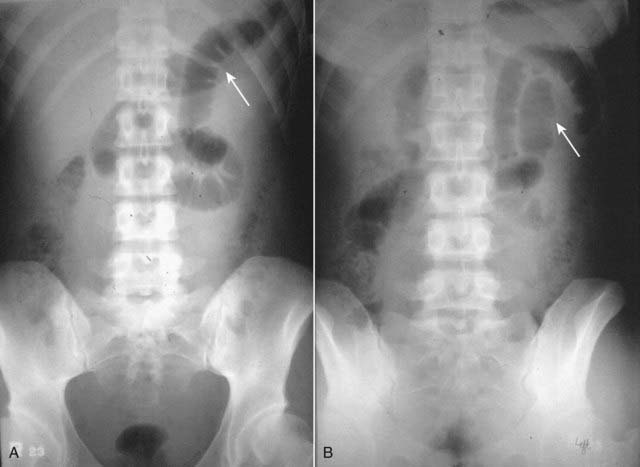

An intermittent, (also known as a partial or incomplete) mechanical small bowel obstruction is one that allows some gas to pass the point of obstruction, at least at times. It can lead to a confusing picture because gas may pass into the colon long after the large bowel would be expected to be devoid of such gas. Partial or incomplete small bowel obstruction occurs more often in patients in whom adhesions are the etiology (Fig. 14-6).

Figure 14-6 Partial small bowel obstruction, supine (A) and upright (B).

A partial or incomplete mechanical small bowel obstruction allows some gas to pass the point of obstruction, possibly on an intermittent basis. This can lead to a confusing picture because gas may pass into the colon (solid black arrows) and be visible long after the large bowel would be expected to be devoid of gas. The important observation is that the small bowel is disproportionately dilated (dotted white arrows) compared to the large bowel, a finding suggestive of small bowel obstruction. Partial or incomplete small bowel obstructions occur more often in patients in whom adhesions are the etiology. Notice the clips (solid white arrows) attesting to prior surgery.